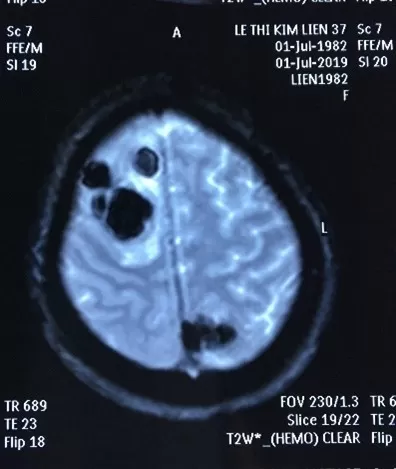

BN nữ L.T.K.L (SN 1987), nhập viện tại thời điểm tháng 07/2019 vì lý do co giật, yếu 1/2 người trái. Bệnh nhân xuất hiện các cơn đau đầu âm ỉ với tần suất tăng dần từ thời điểm trước khi nhập viện 4-5 tháng, đã đi khám tại một số bệnh viện và điều trị không giảm, bệnh nhân sau đó xuất hiện cơn co giật, được đưa vào cấp cứu tại BV Bạch Mai, hình ảnh chụp MRI sọ não cấp cho thấy các khối di căn lan toả 2 bán cầu, chủ yếu bán cầu não phải, hình ảnh cắt lớp vi tính ngực gợi ý tổn thương nguyên phát từ phổi. Bệnh nhân được giải thích tình trạng nặng, sau đó được chuyển sang BV Ung Bướu Hà Nội điều trị giảm nhẹ. Rất may mắn tại bệnh viện Ung Bướu Hà Nội, bệnh nhân được rà soát các tổn thương toàn thân và cuối cùng được sinh thiết hạch cổ làm chẩn đoán. Giải phẫu bệnh hạch cổ có kết quả di căn ung thư biểu mô tuyến nguồn gốc phổi, xét nghiệm giải trình tự gen cho kết quả dương tính với đột biến tái sắp xếp ALK. Bệnh nhân được tiếp cận điều trị thuốc kháng ALK thế hệ 2- Ceritinib, chỉ sau 1 tháng bệnh nhân hồi phục hoàn toàn các triệu chứng về thần kinh trung ương, đi lại vận động sinh hoạt như bình thường. Kết quả chụp lại MRI sọ não và CLVT ngực sau 02 tháng điều trị cho thấy hình ảnh đáp ứng sớm và ngoạn mục với liệu pháp nhắm đích.

Hình 4: tổn thương di căn não trên MRI trước điều trị